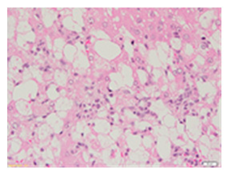

Liver wet weights of all rat groups showed no significant differences (Table 8). According to histochemical hematoxylin and eosin (H&E) staining, treatment with the highest dose of MPE (1000 mg/kg BW) did not result in morphological changes in the liver tissue (B) when compared with DI water treatment (A). Obviously, CCl4 induction (ip)/DI water treatment (po) caused hepatoxicity, which was indicated by a severe degree of fatty changes and fatty cysts in the liver tissue (C), whereas pretreatments of silymarin (100 mg/kg BW, po) effectively decreased the degree of fatty changes and fatty cysts in the liver when compared with the CCl4/DI water group. Indeed, MPE (250 and 1000 mg/kg BW, po) lowered the degree of lipid accumulation in the liver; inversely, MPE (500 mg/kg BW, po) exhibited a severe degree of lipid accumulation. Apparently, taking paracetamol (2 g/kg BW) induced a severe degree of hepatic necrosis when compared with rats that had not received the treatment. Similarly, pretreatments of silymarin (100 mg/kg BW, po) and MPE (250 and 1000 mg/kg BW, po) revealed a mild degree of hepatic necrosis, while MPE (500 mg/kg BW, po) revealed a moderate to severe degree of hepatic necrosis. Accordingly, the findings imply that the consumption of MPE (1000 mg/kg BW) was not harmful to the liver of healthy rats, while MPE (250 mg/kg BW) did improve fat deposition in the livers of CCl4-fed rats and offered protection against liver cell damage in paracetamol-fed rats.

Wet weight values (mean ± SD) and H&E staining of liver from rats with hepatotoxicity induced by CCl4 and paracetamol.